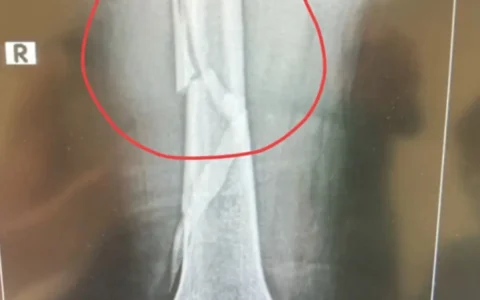

#文章首发挑战赛#​ 向太陈岚,最近遇到了一件糟心事,就在4月26日,她发布视频表示,自己在浴室的时候摔倒了,最后检查为大腿骨断裂,在手术之后,她的举动更是把医生都吓坏了。 另外我们看了公布出来的检查报告之后,发现还是伤的挺重的,能够明显的看到腿骨断裂的痕迹,这光片看着真的很吓人,不知道她当时该有多么的痛啊!向太表示自己并没有掉泪,如果换做一般人的话,我觉得…